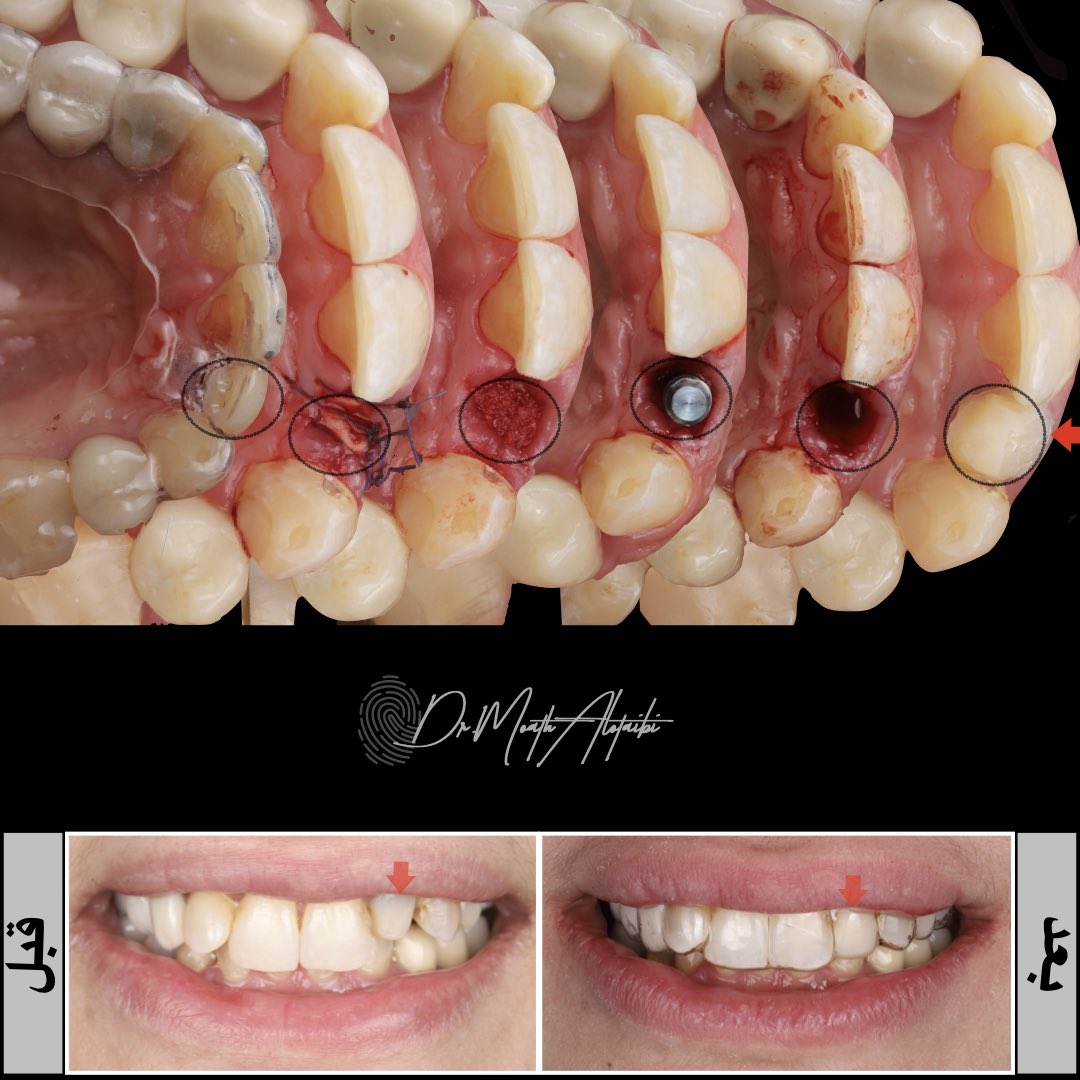

من مراحل اعادة تأهيل كامل للفكين عن طريق الزراعه.. تم فيها علاج بروز الاسنان واعادة الاطباق الوظيفي والجمالي للمراجع بالتعاون مع د.مشاري المطيري مشاري بدر بن زريبان في قسم التركيبات الثابتة والمتحركه #زراعة_الاسنان #التركيبات_الثابته #التركيبات_المتحركه

ردينا ابتسامتها بشكل افضل وعالجنا البروز😍 استخدمت فيها احدث الطرق للمحافظة على العظم المحيط بالاسنان وترميمها بالسبل المثالية والمثبته علميا. الجراحة وزراعة العظم و الاسنان معاي والتركيبات مع د.نواف القاضي نـواف الـقـاضـي ❤️